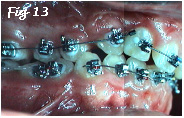

2) La canine permanente peut faire son éruption dans un os normalisé. (Fig.12). Elle pourra être redressée, alignée (Fig.13) et rapprochée des dents voisines en conservant un support osseux normal (Fig.10 & 11).

3) La dépression labiale que l'on déplore parfois au niveau de la fente, est réduite du fait du comblement de la fente. Le support de l'aile du nez (narine) est amélioré et l'asymétrie minimisée.